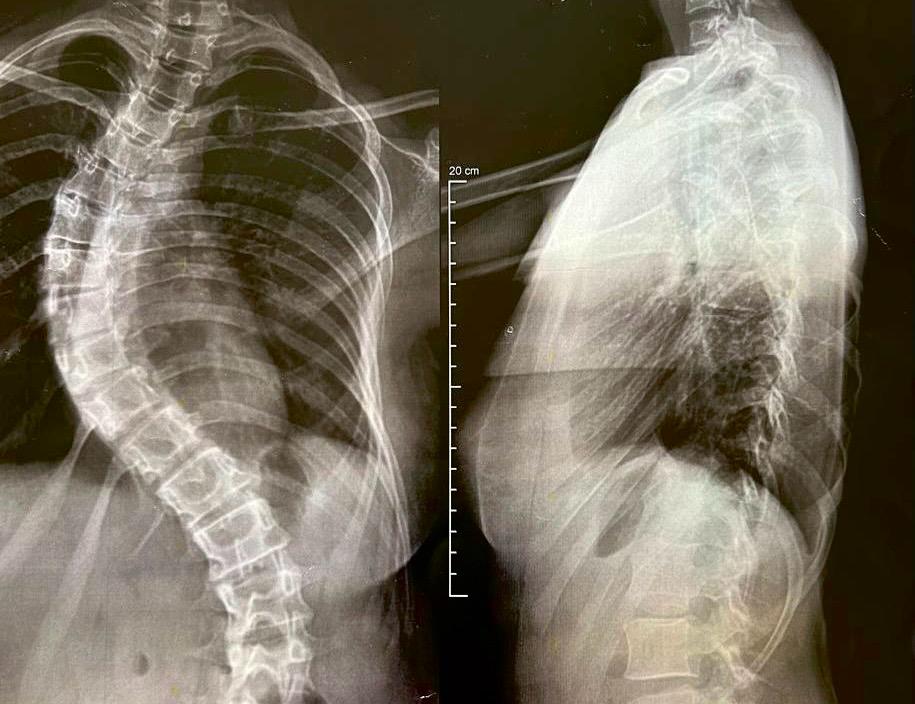

O Hospital São Vicente de Paulo, de Passo Fundo, realizou nesta quinta-feira (28) a primeira cirurgia utilizando uma mesa cirúrgica de última geração, o Sistema Espinhal Allen Flex, em uma paciente de 17 anos com diagnóstico de escoliose. O procedimento foi feito por meio do Sistema Único de Saúde (SUS) e foi conduzido pelo cirurgião ortopédico Luís Gustavo Calieron, responsável pelo Serviço de Escoliose do HSVP, com a participação do neurofisiologista Fernando Giacomini, anestesista Nelson Rafael Barros Fauth e do médico residente Robson Luiz de Souza Alhadas.

Desde o início da iniciativa, o Dr. Calieron realizou 70 cirurgias pediátricas para correção da escoliose, contribuindo significativamente para agilizar o acesso ao tratamento e melhorar a qualidade de vida dos pacientes. Os casos atendidos no hospital costumam ser complexos, apresentando curvaturas severas da coluna, podendo causar dores, limitação dos movimentos, além de impactos respiratórios e nutricionais.